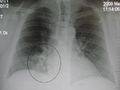

Pneumonia as seen on chest x-ray. A: Normal chest x-ray. B: Abnormal chest x-ray with shadowing from pneumonia in the right lung (white area, left side of image).